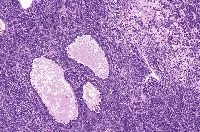

This is an AI laboratory project by Linette Dannah Cartagena, a second year medical student. Ovarian cancer can be classified into four main types: epithelial tumors, germ cell tumors, stromal tumors, and small cell carcinoma of the ovary. This model aims to recognize each type through AI. All one has to do is to simply by upload a photo of the histological slide.